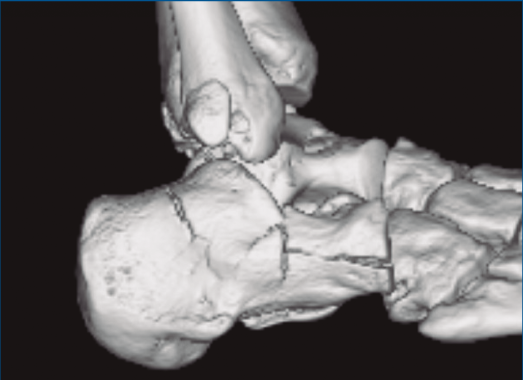

Figura 2. Fractura maléolo peroneo y tibial posterior. Trazo entre fragmento anteromedial y posterolateral.

Figura 3. Desplazamiento entre fragmento anteromedial (sustentaculum tali) y posterolateral (tuberosidad).

Se trata de un varón de 19 años que ingresa en reanimación tras precipitarse desde una altura de aproximadamente 10 metros. El paciente presenta una fractura estallido de L3 con afectación del canal medular junto con una fractura del vértice inferior de L4, así como una fractura luxación de calcáneo, asociada a una fractura del maléolo peroneo y del maléolo tibial posterior (Figuras 1 a 6) diagnosticadas mediante TC total body (por eso no se dispone de radiografías simples al momento del ingreso). Como podemos comprobar, se trata de una fractura de doble trazo de tipo hundimiento/depresión de la carilla articular (Figuras 5 y 6).

Figura 5. Fractura maléolo peroneo, luxación astrágalo, fractura de doble trazo en calcáneo.

Figura 6. Fractura de doble trazo; se evidencia afectación de la articulación calcaneocuboidea.